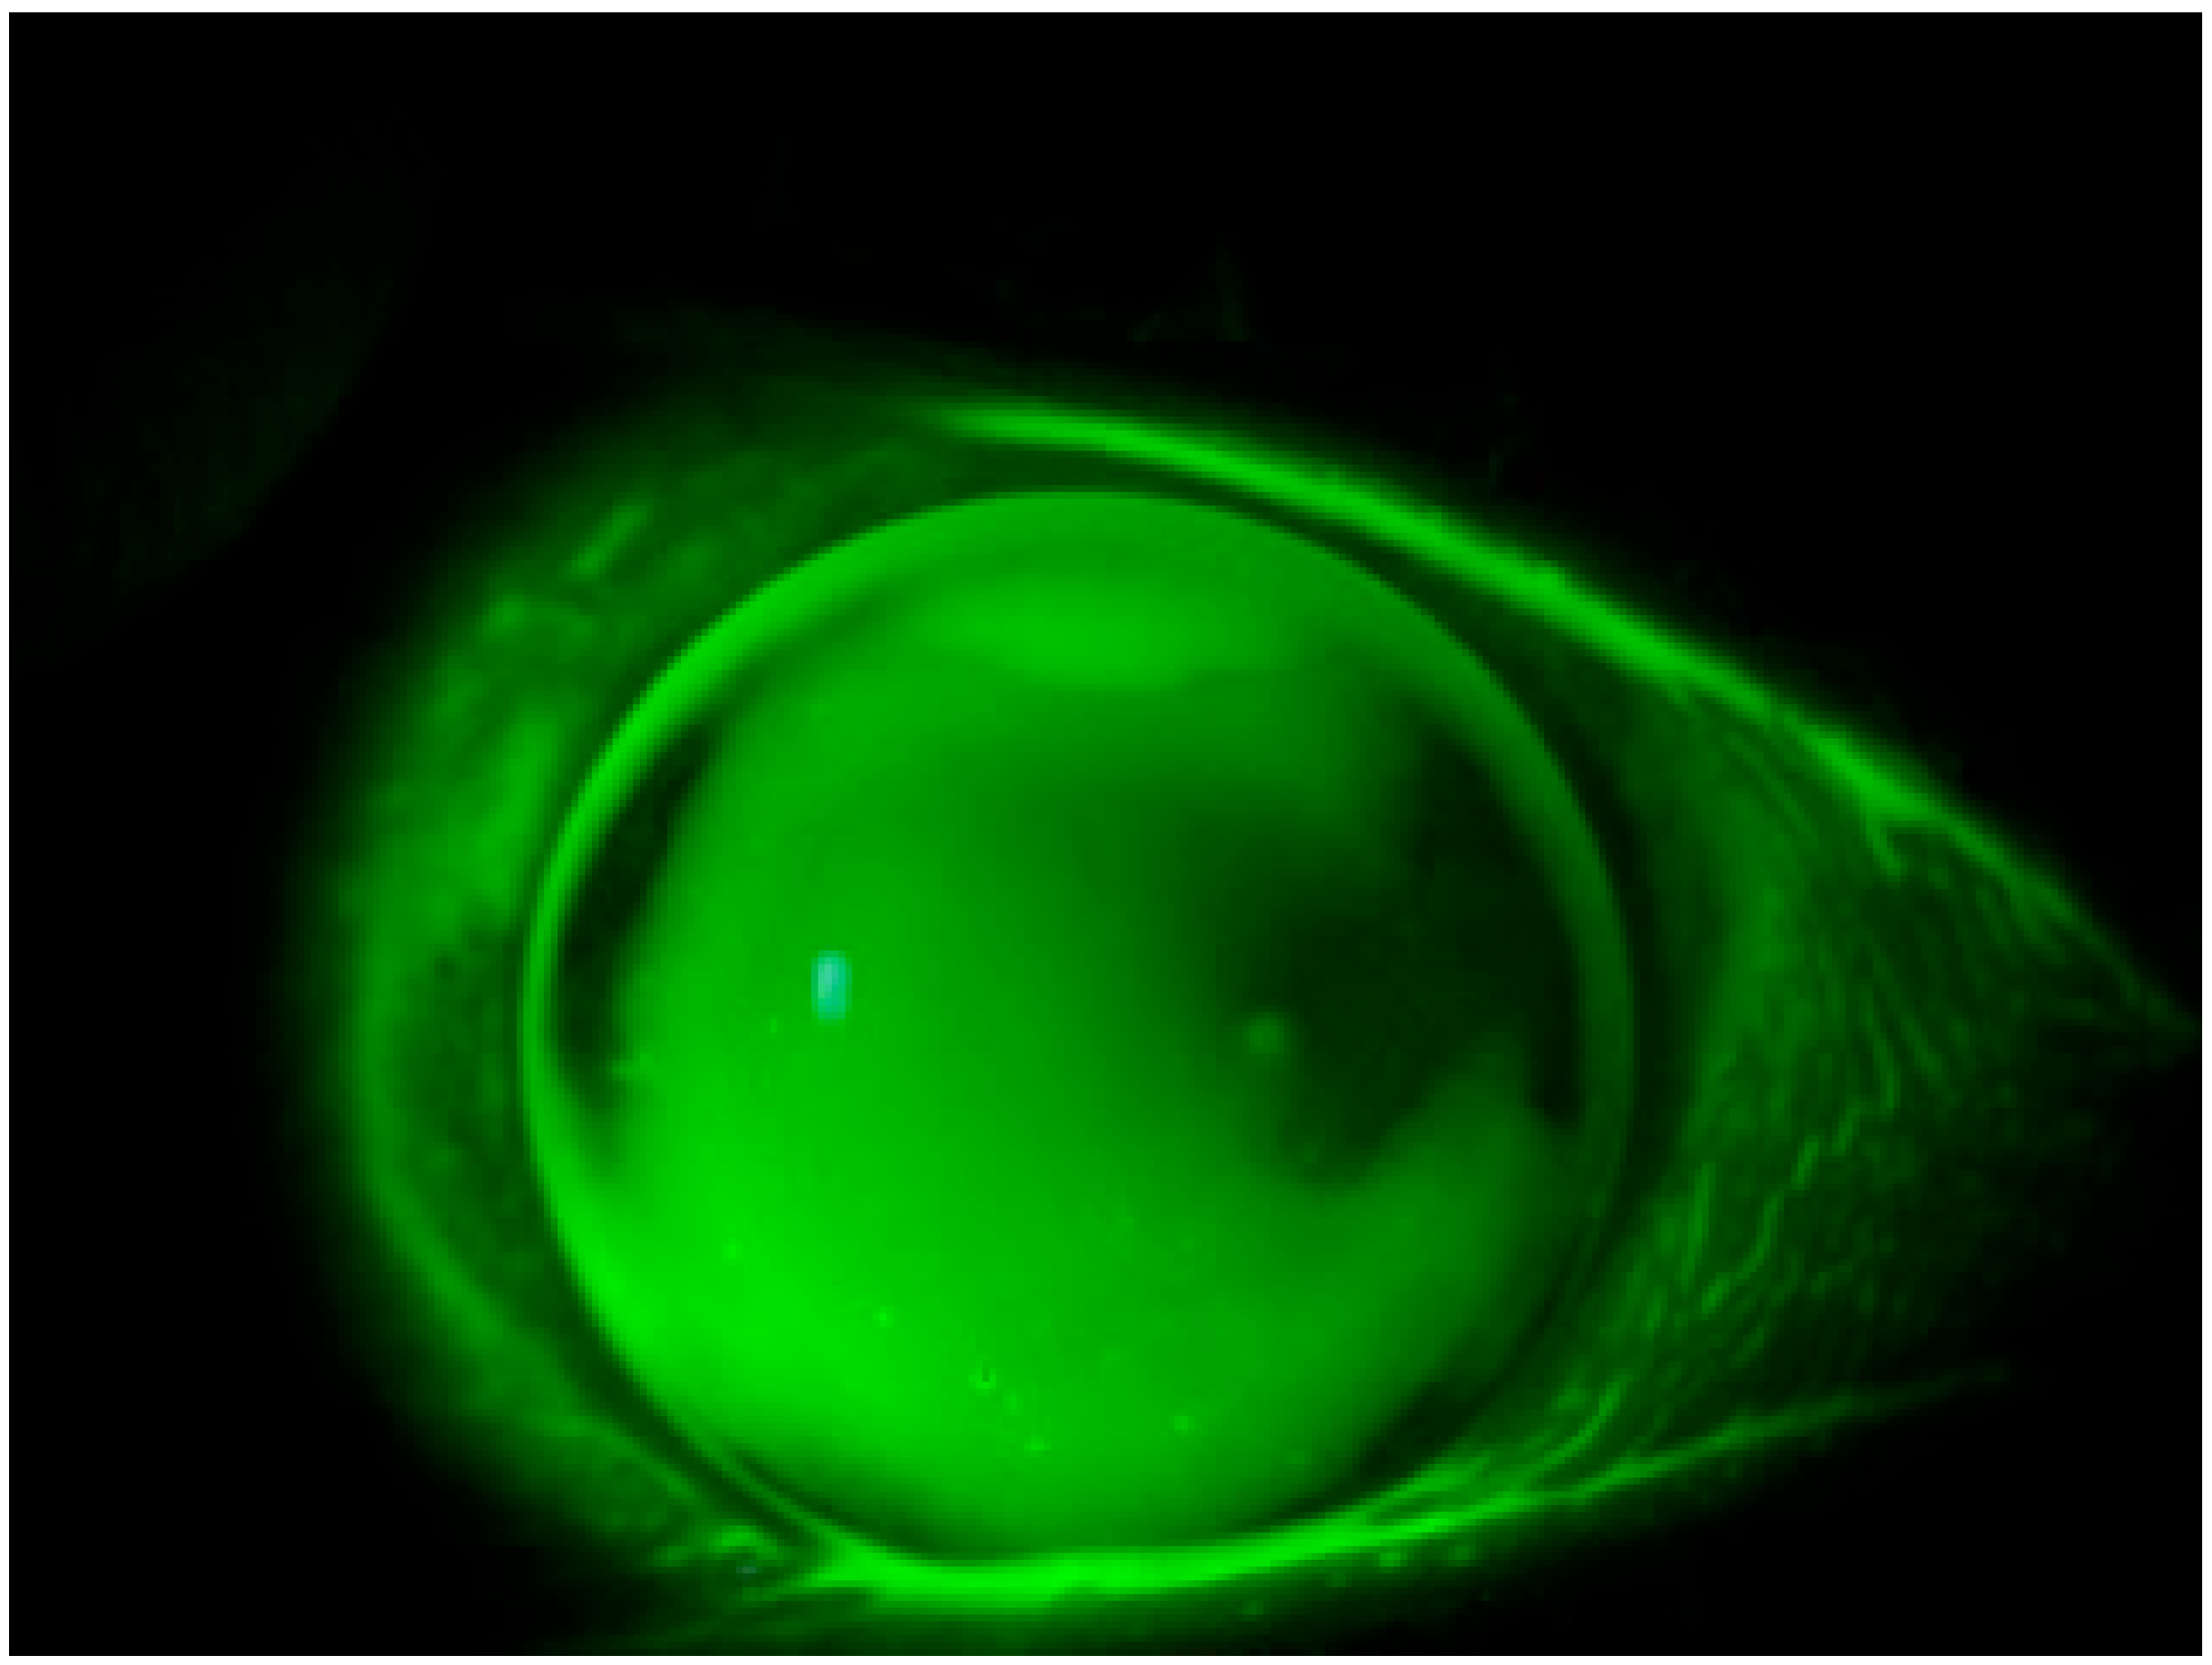

- Compatibility with Contact Lenses: unlike NaFL, diagnostic riboflavin can be used as a diagnostic stain even in the presence of soft contact lenses. The staining effect is temporary, thereby minimizing the risk of adverse effects on the ocular surface.

- Visual Inspection: utilizing a stereomicroscope, each contact lens underwent meticulous visual inspection to detect any imperfections, opacity, or irregularities along its edges.